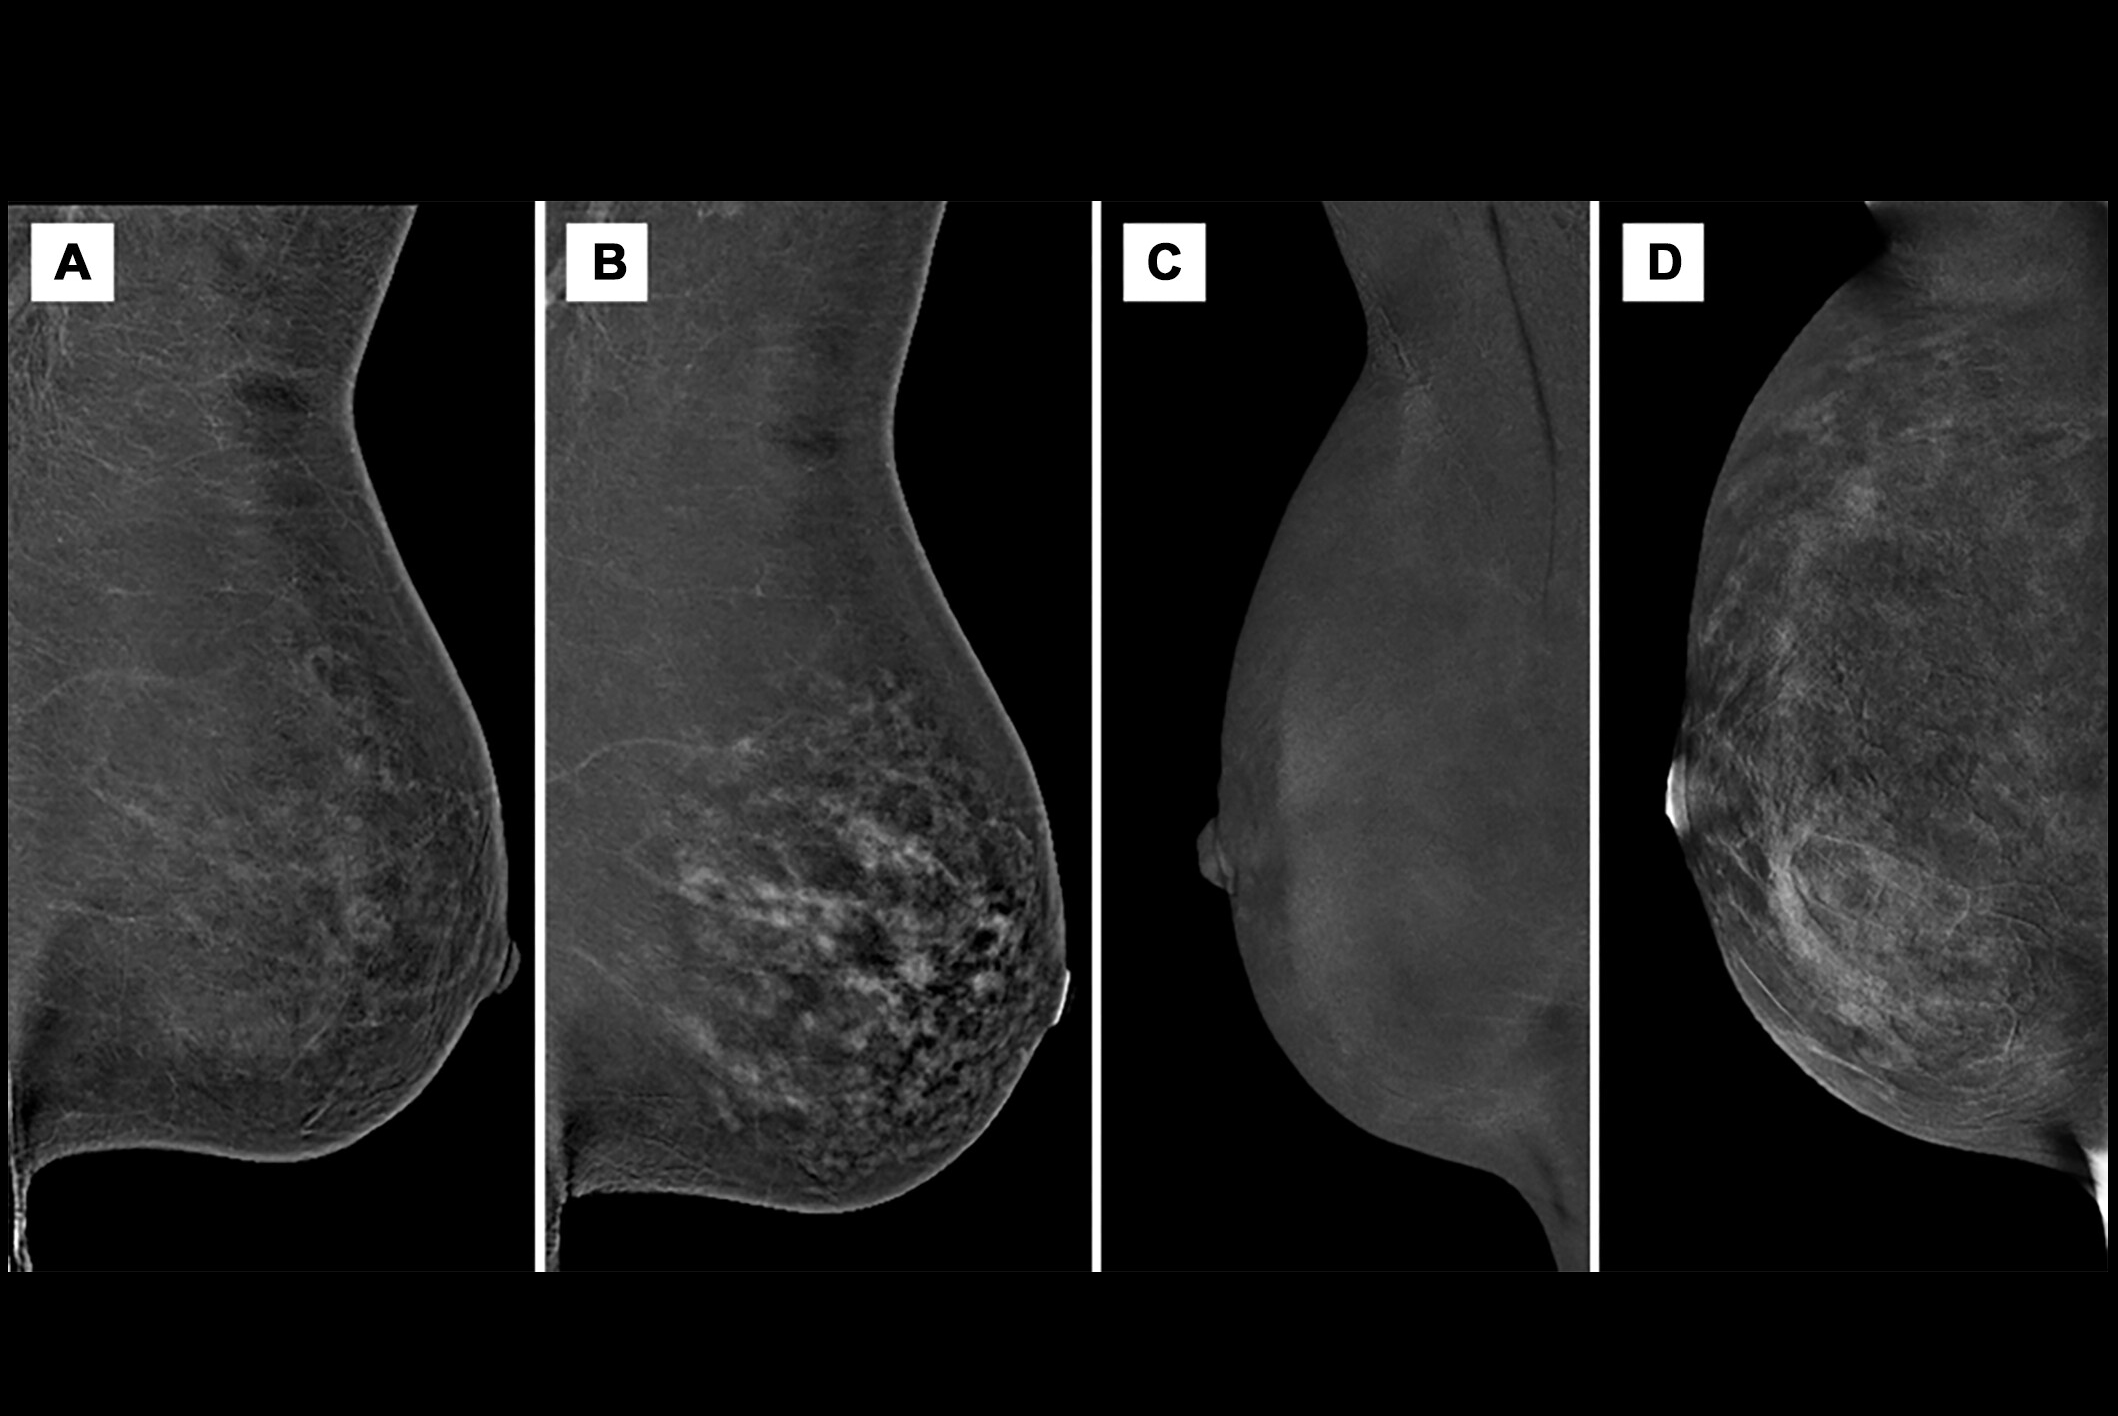

CBBCT in previous studies has shown advantages over supplemental breast MRI and ultrasound. The researchers highlighted the modality’s ability to assess breast calcifications and hemodynamic features at the same time. These studies also suggest that CBBCT could have value in breast cancer diagnosis, tumor size assessment, and molecular subtype prediction.

Ye and co-authors investigated potential ties between contrast-enhanced CBBCT imaging features and LVI status in breast cancer patients. The study included data collected between 2020 and 2023 from 401 women who underwent this imaging exam. Two radiologists reviewed the image features independently.